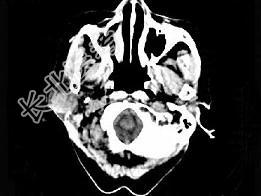

- 单项选择题女,72岁, 六年前于右面颊部扪及一包块,缓慢增大, 其表面较光滑,CT如图所示, 该病例应诊断为 ( )

A、Worthin瘤

B、腮腺混合瘤

C、颈部神经纤维瘤

D、颈部淋巴瘤

E、小唾液腺瘤